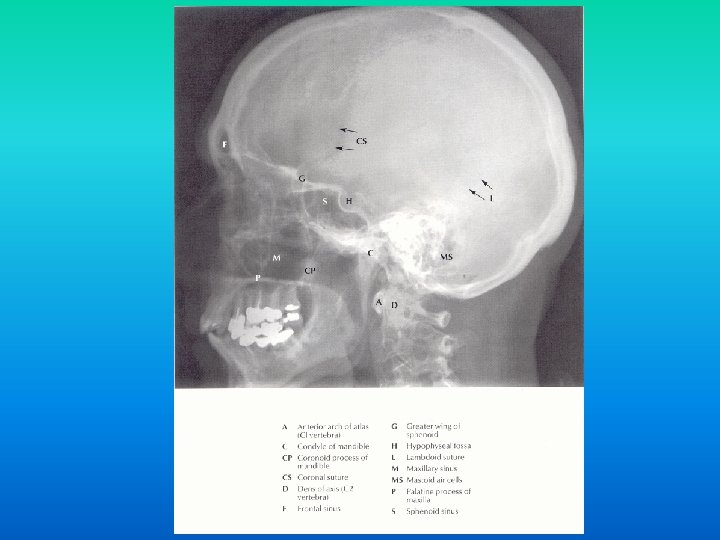

Tehnici de explorare radioimagistica n in functie de bazele fizice sunt: n tehnici ce utilizeaza razele X: n n radiografii, mielografii, CT tehnici imagistice ce utilizeaza alte modalitati de obiectivare a structurilor anatomice: n ecografia, IRM